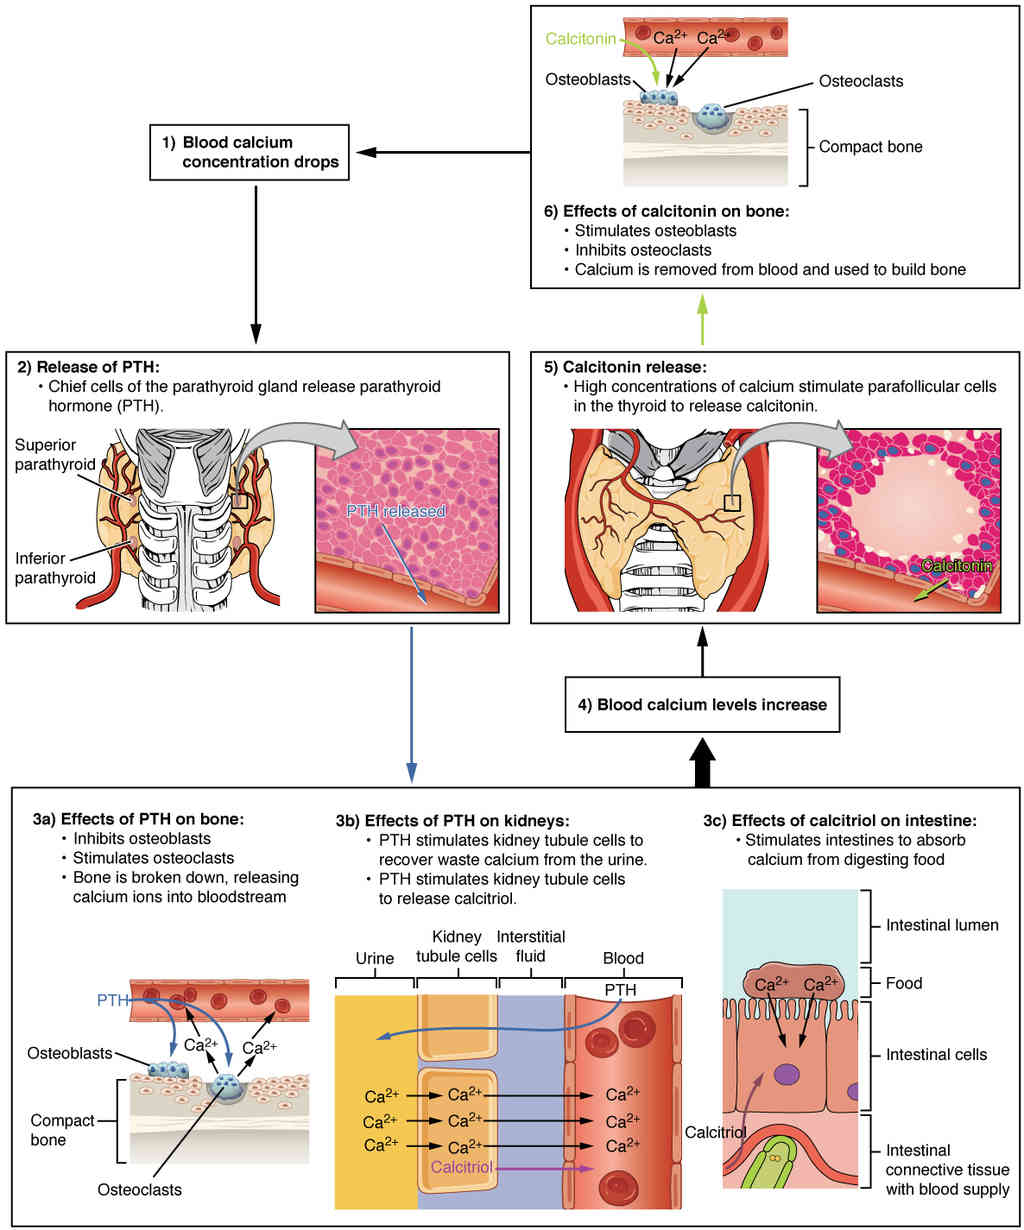

This page is under construction. For now, it is just a resource of the images found in the OpenStax Anatomy and Physiology Handbook. It wil slowly change into a revision tool. Each slide has a number. Use this to refer to the slide. When completed, it will have an unlabelled section, with labelled slides in parallel. On the unlabelled slides, write your answer and use the labelled slide to assess yourself. Keep track by also noting the number on each slide. Improvement at each attempt is important, more so than full marks on a first attempt.